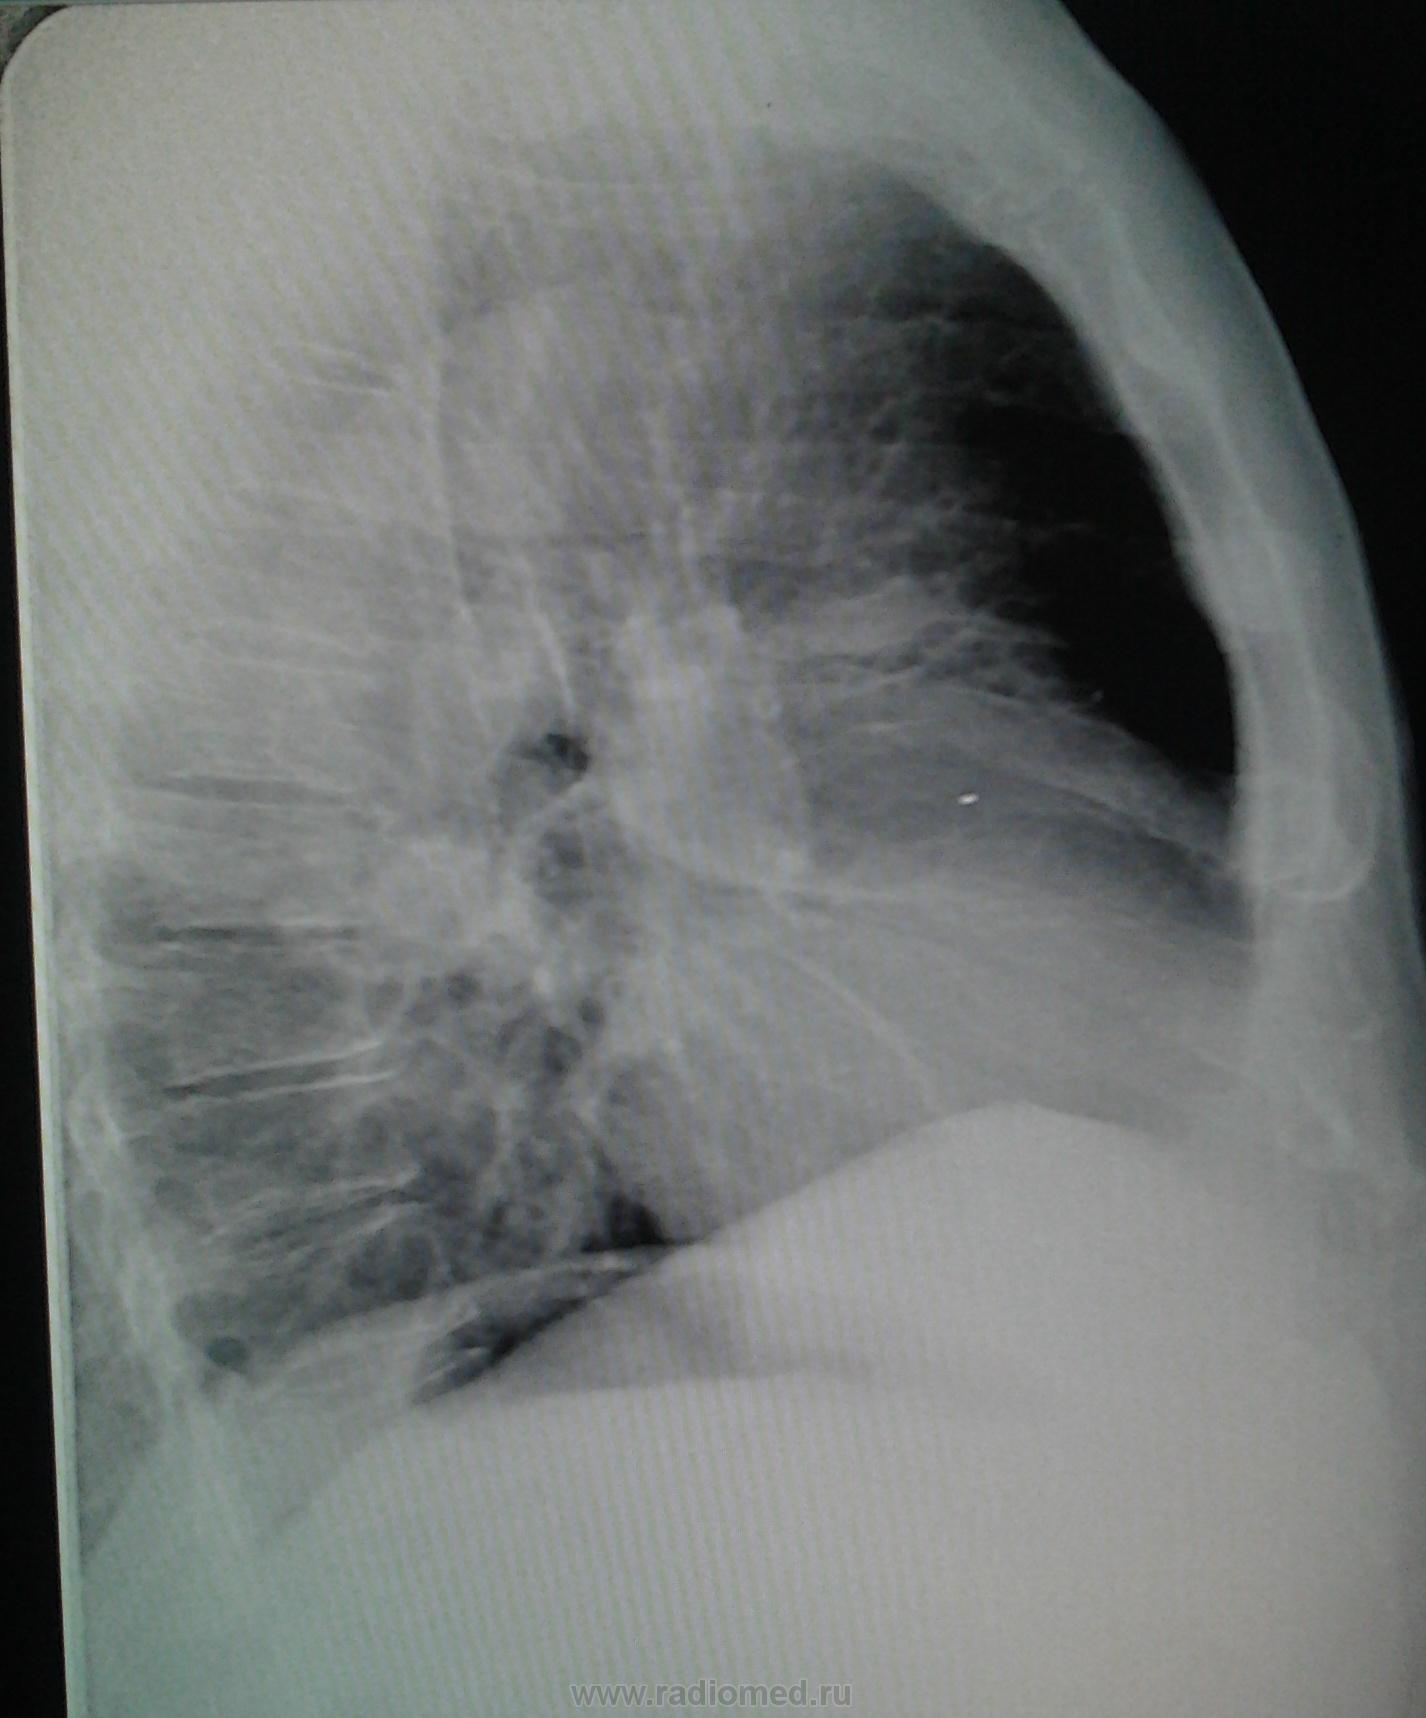

Мужчина 1956 г.р,проф.флг,жалоб со стороны легких не предъявляет,температура нормальная,посмотрела в амб.карте- последняя флг в 2008 году,там была норма,сейчас лечится у невролога по поводу межреберной невралгии.Можно ли расценить тень справа в тройке как фиброз?

Тут так сразу и не скажешь.Если свежего архива нет,надо наблюдать в динамике.Тень справа нехорошая,просится на томографию,желательно,компьютерную.Линейная тоже может внести некоторую ясность.

Крайне не красивый "фиброз". Рачком попахивает. Лучше сразу проконсультировать у онколога, а за одно уж и у фтизиатра.И контроль за ним обязателен.

С другой стороны тоже или фиброз, или дисковидный ателектаз. Возможно была пневмония с двух сторон. Наблюдение.

И здесь тоже, кажется, плохи дела, и опять в корне уже. А точно межреберная невралгия у него? И справа? Наводит на размышления. Поспрашивайте, если можно анамнез в ближайшие 3-5месяцев. Ничем не болел? Слева тоже изменения.